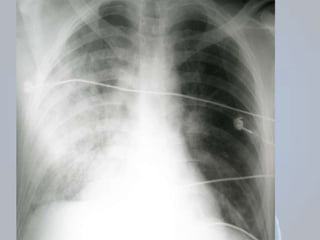

• #27  A radiografia 3 mostra contusão pulmonar à direita.

• #28  A radiografia 1 mostra contusão pulmonar à direita e discreto enfizema de subcutâneo à direita.